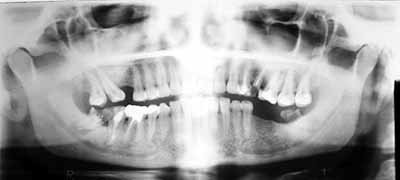

OPG & Cephalogram

What

is OPG?

OPG stands for Orthopantomography. It is a special method for obtaining

radiographs of the teeth-bearing jaws, both upper and lower.

How is it different from regular X-ray machines?

A regular X-ray machine cannot take detailed pictures of the jaw-bones. An OPG

machine is specially constructed so that it rotates around the jaw-bones, thus

giving us an extremely good idea about the structure of the jaw bones. Yes,

x-rays are used, but the method is totally different.

In what situations are they needed?

OPG x-rays are usually asked for by dentists, whether they be general dentists,

orthodontists, oral surgeons or prosthodontists/implantologists. Because OPGs

give a bird-eye view of the teeth and the adjacent bones, they are useful in a

wide-variety of conditions including infections, tumors, congenital

abnormalities, pre-implant evaluation and trauma.